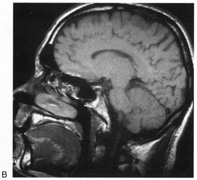

Fig. 15. Bilateral incomplete hemianopia. A 69-year-old man with decreased vision after prostate surgery. A. Fields show remaining central parafoveal vision with some sparing of inferior left quadrant. Note how the defect respects the vertical meridian. B. MRI shows bilateral medial occipital infarction, with sparing of the occipital poles, accounting for the macular-sparing bilaterally. (Courtesy of Dr. Lucia Vaina.)

Bilateral lesions of striate cortex are not rare. Focal midline lesions such as tumors or traumatic injury may affect both striate cortices concurrently, because the right and left striate cortices face each other on the medial occipital surface. The most common cause, however, is posterior circulation ischemia.57 This can affect both striate cortices either simultaneously or sequentially,57 because the right and left posterior cerebral arteries have a common origin from the basilar artery. Twenty-two percent of patients with a unilateral occipital infarction develop bilateral infarction over 3 years.58 Bilateral incomplete hemianopia is distinguished from bilateral optic nerve or ocular disease by the high congruity of the visual fields and step defects along the vertical meridian which indicate the hemifield nature of the visual loss (Fig. 15).57 Such steps are important to seek with a skilled perimetrist, but even so they can be difficult to demonstrate with bilateral hemiscotomata from occipital pole lesions.59 Bilateral quadrantanopias can occur,47,48 often in patients with prosopagnosia and achromatopsia for example, and may mimic the altitudinal defects of optic neuropathy.